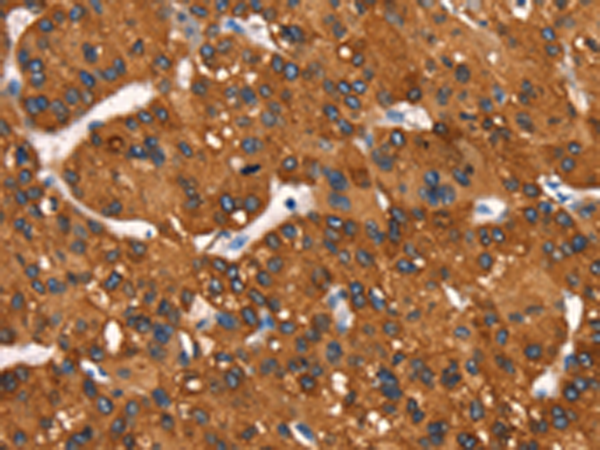

IHC positive control: |

Human liver cancer and Human gastric cancer |

IHC Recommend dilution: |

50-200 |